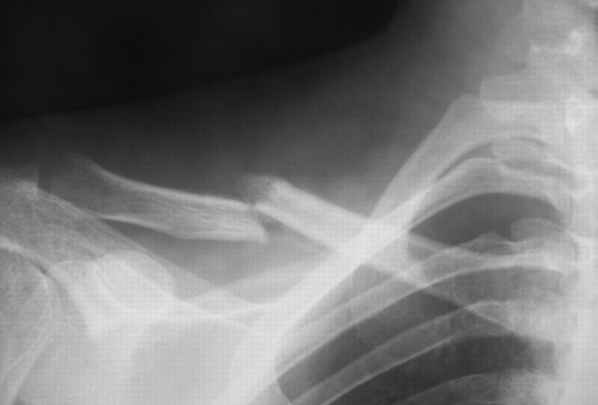

Один из вариантов, что удалось быстро найти, позже еще найду, но схема примерно такая (первое

вложение).

Мужик кочегар, срок нетрудоспособности 7 недель. Наружную конструкцию сняли через 3 недели. Далее без иммобилизации. Погруженную спицу можно убрать и через несколько месяцев, если жить не мешает.

Раньше не погружали, на рентгенограммах и натуре видно (последние 2 вложения). Как вариант спицы в периферическом отломке могут крепится на трехдырочную приставку, что дает возможность компрессии.